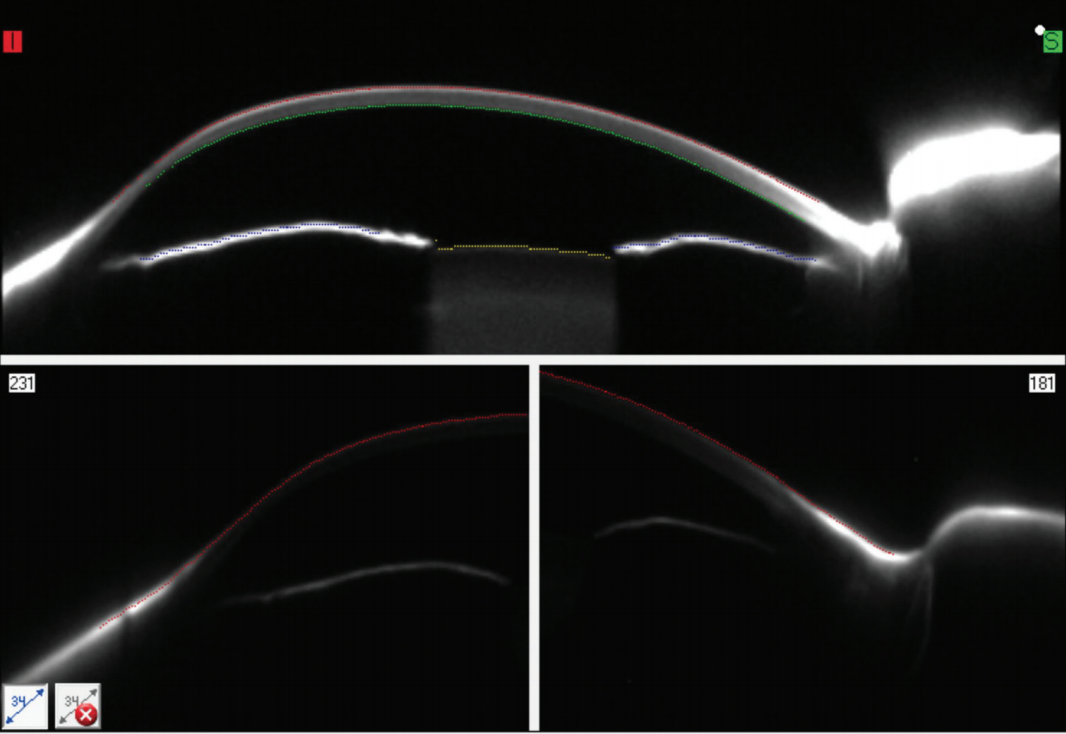

Pentacam CSP Software to Improve Efficiency and Efficacy of Complex What Is Lens Retraction Web i am just getting acquainted with it and have a pretty basic question: Lens calibration should be done if you notice consistent camera misfocusing issues. This refers to the lens being in an extended operating. Web in short, “canon camera lens won’t retract” is a common issue where the lens remains extended or gets stuck, hindering its smooth retraction. What Is Lens Retraction.